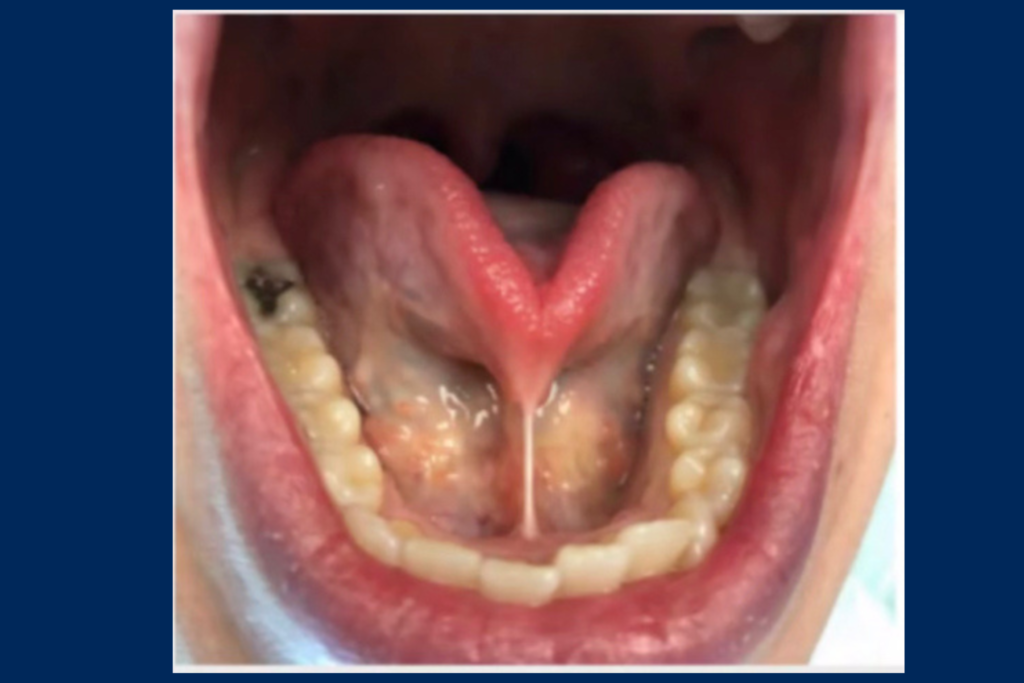

Read MoreThe Tongue Tie. By: Dr. Nishita Ondhia

The tongue plays an important role in proper swallowing, nasal breathing, jaw development, TMJ stability and sleep quality. When it is restricted, tied or tethered the body will compensate and different symptoms will cascade. Some areas of symptoms are as follows: Feeding and Speech Sleep and Breathing Face and Jaw Development Behaviour and learning Feeding…